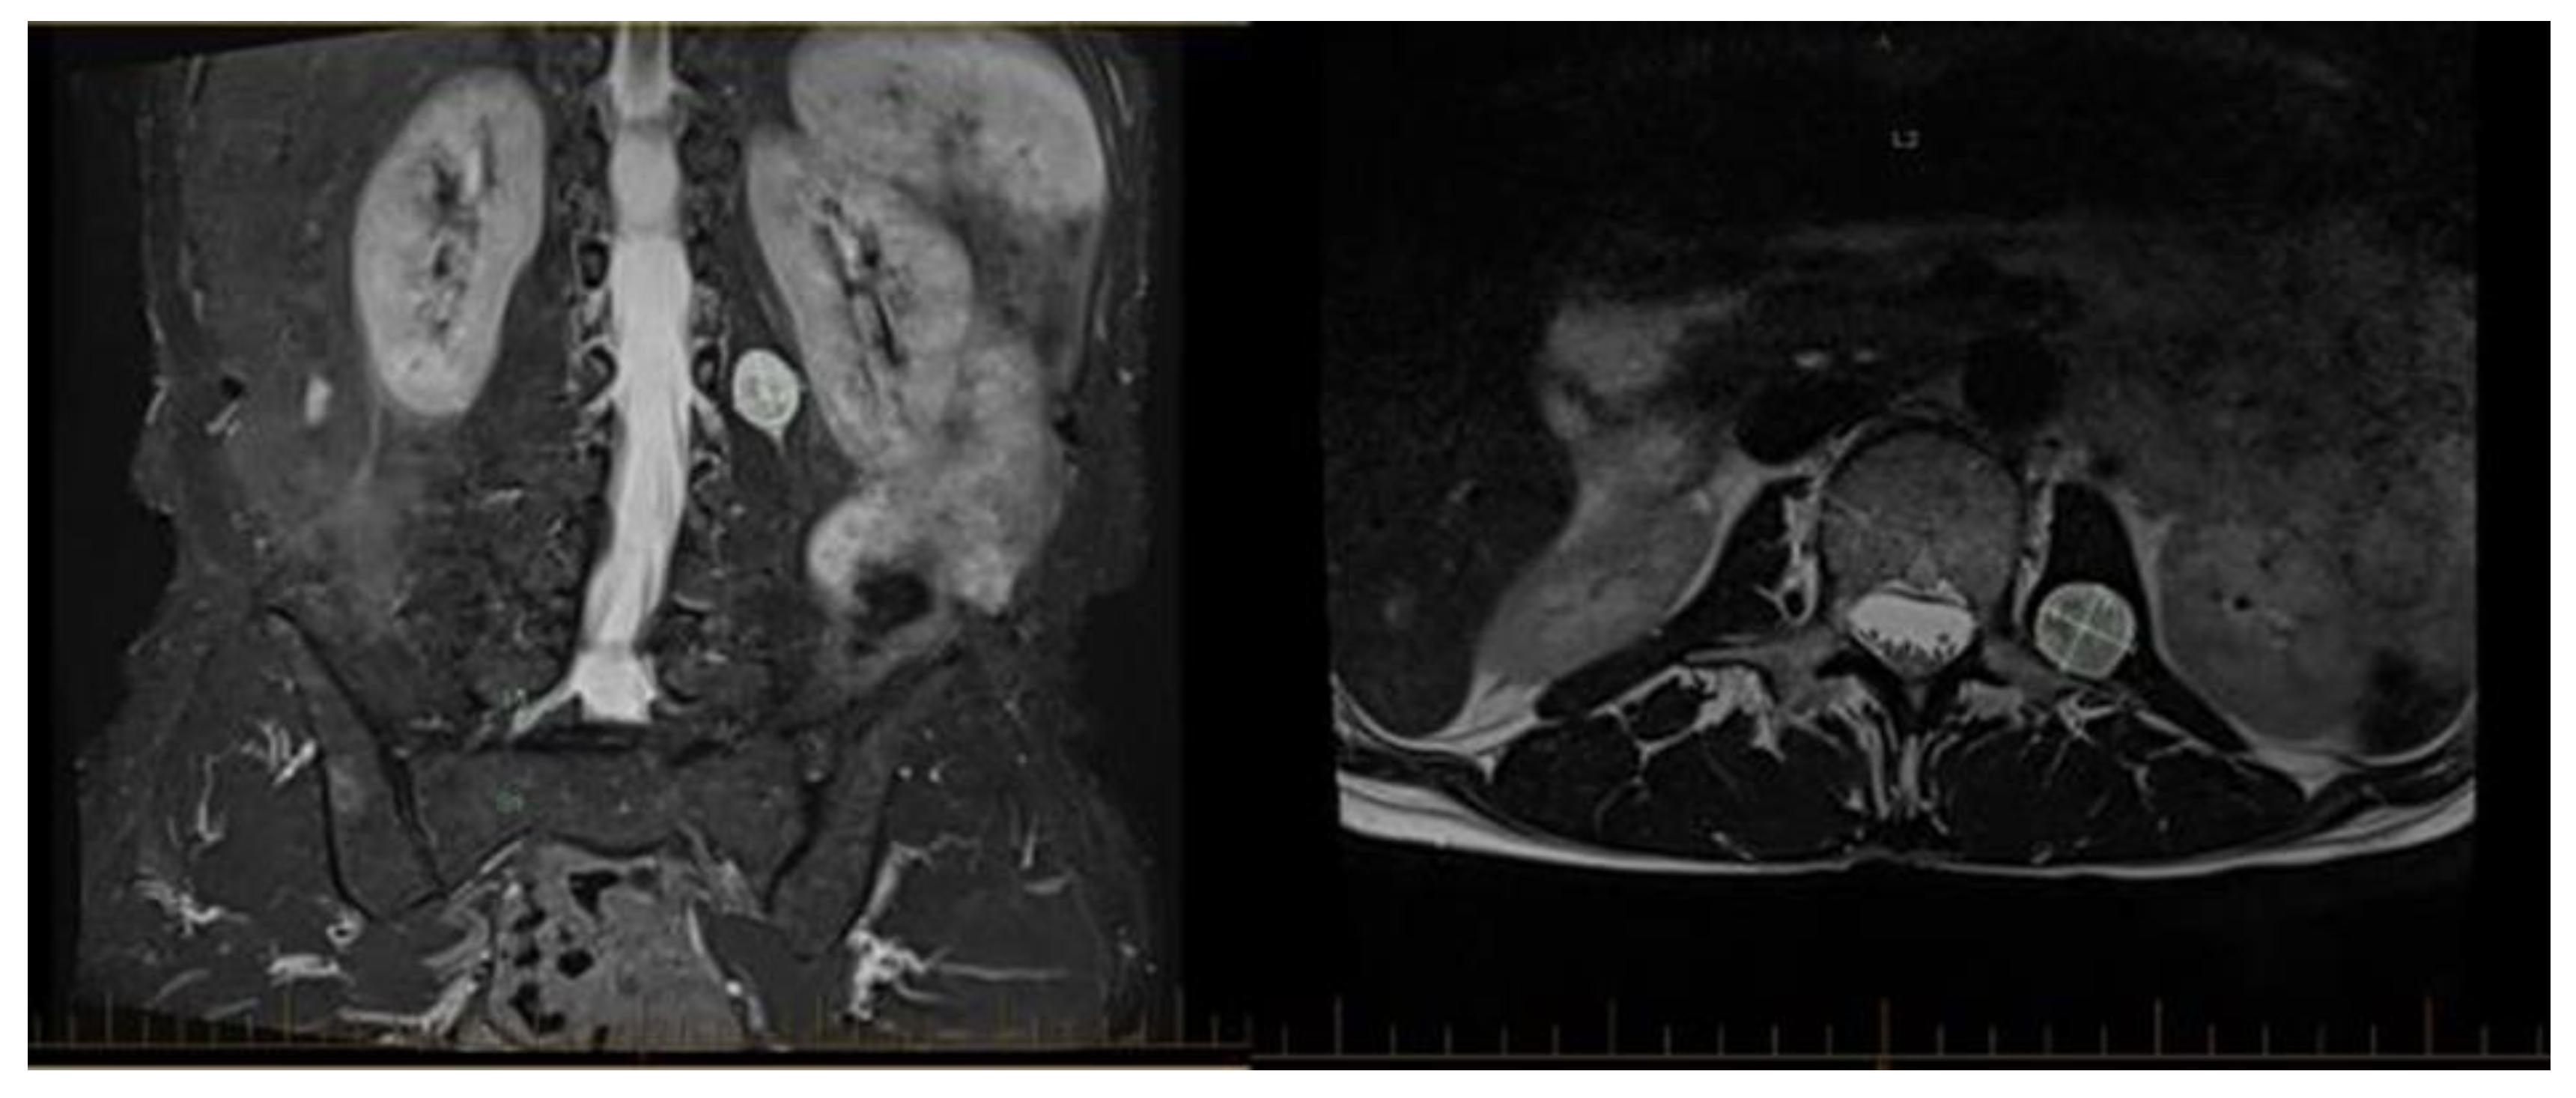

- Perica, E.; Sun, Z. Patient-specific three-dimensional printing for pre-surgical planning in hepatocellular carcinoma treatment. Quant. Imaging Med. Surg. 2017, 7, 668. [Google Scholar] [CrossRef]

- Bernhard, J.-C.; Isotani, S.; Matsugasumi, T.; Duddalwar, V.; Hung, A.J.; Suer, E.; Baco, E.; Satkunasivam, R.; Djaladat, H.; Metcalfe, C.; et al. Personalized 3D printed model of kidney and tumor anatomy: A useful tool for patient education. World J. Urol. 2016, 34, 337–345. [Google Scholar] [CrossRef]

- Patient education is a crucial aspect of patient-centered care, and healthcare providers prioritize effective communication. Presenting imaging reports verbally or displaying CT and MRI scans to patients often falls short, as these 2D representations may not fully convey the complexities of 3D anatomy. In contrast, 3D printing offers a promising solution, enhancing doctor-patient communication by directly showcasing anatomical models [77,78].